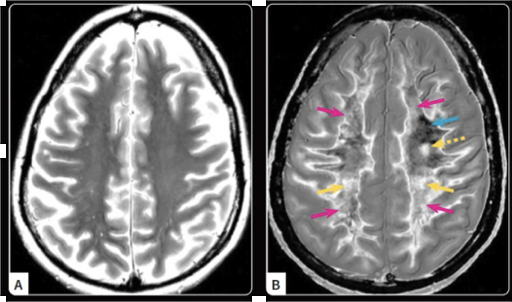

MS in remission on standard scan (A), which showed no clear problems. Using UHC (B), the scan revealed subtle signs of MS: a small lesion, changes in key movement pathways, and patches of abnormal white matter.

Ultra-High Contrast (UHC) MRI is a breakthrough technique that dramatically improves visibility in brain disorders. The technique is showing strong promise in transforming how we detect and monitor diseases affecting the brain and nervous system, including mild traumatic brain injury (mTBI), Alzheimer's disease, and early multiple sclerosis (MS).

This innovative method enhances the contrast between healthy and affected tissues by targeting subtle changes in tissue properties, such as T1 relaxation times.